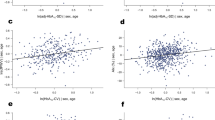

Lower FMD was associated with increasing age (r = −0.72, p = 0.001) and higher systolic BP (r = −0.50, p = 0.04). Subjects with high fasting triglycerides (≥1.69 mmol/l) had lower FMD scores than subjects with low or normal fasting levels (mean FMD = 3.76±0.74 vs 6.31±0.66, p = 0.03). None of the other demographic, metabolic or cardiovascular-risk variables were significant predictors of fasting FMD, and fasting glucose was not related to fasting FMD in individuals either across visits or in the sample as a whole (Fig. 1).

The primary measure of variability was the mean difference between three pairs of measurements, expressed as an absolute value (Table 3). Variability in FMD was positively correlated with variability in glucose (r=0.52, p=0.03), insulin (r=0.47, p=0.05) and heart rate (r=0.48, p=0.04), despite the fact that FMD was not related to absolute levels of these parameters. In multivariate analysis, only mean variability in glucose remained an independent predictor, accounting for 35% of the variance in FMD variability. FMD variability was unrelated to fasting glucose or any of the other health-related variables examined (HbA1c, age, BMI, BP and lipids). Results were unchanged when adjusted for the number of days between visits.

Nevertheless, the reported CVs for FMD (in this study, and in many others) are higher than those conventionally accepted for biochemical assays. As noted previously, variability in FMD is likely to result from the combined effects of measurement error, real biological variability and subtle differences in the application of the technique over repeated testing sessions [20]. We found that subjects with more variable values for glucose, insulin and heart rate also showed the greatest variation in FMD across testing days. Variability in glucose was the only independent predictor of variability in FMD.

These results suggest that true biological variability is a significant source of variation in FMD scores. However, the lack of a correlation between fasting glucose concentrations and fasting FMD scores indicates that the relationship between glucose and FMD is complex. It is possible that larger day-to-day fluctuations in glucose are a marker of more advanced disease, and that FMD variability may be even greater in individuals with poorly controlled diabetes. In as far as heart rate, glucose and insulin levels can be controlled by careful subject selection and instruction, researchers are advised to account for these variables in their study design and analyses.